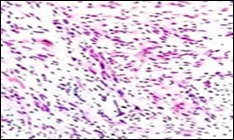

Figure 11.Soft tissue perineurioma with whorls of neural cells delineating spindle cells with bipolar cytoplasm and wavy nuclei and an admixture of collagen bundles 19.